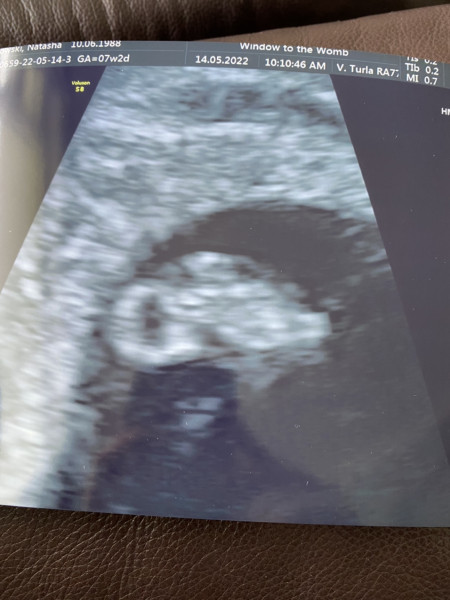

Afternoon ladies, well had our private scan this morning and everything is perfect! We got to see the heartbeat beating away perfectly 🙂. Measuring exactly how we thought so still 7w 2d. Baby was resting their head on the yolk sack and relaxing away haha. So glad I can settle and rest a little now. NHS scan in 2 weeks time so hopefully get a clearer photo!

@tasha4eva10 your scan looks great. You can see so much at just 7 weeks!